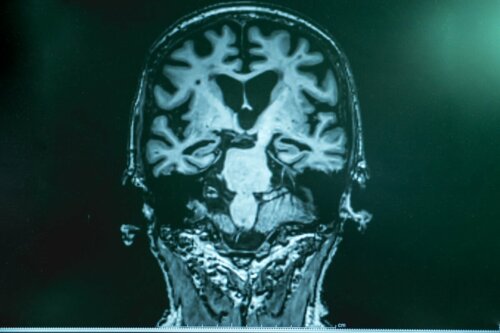

Brain Wave Stimulation for People with Alzheimer's

Do you know what gamma waves are? Are you aware of the benefits of wave brain stimulation as a treatment for Alzheimer’s disease? The advancement of science and technology and their relationship have allowed the development of new treatments that are literally a ray of sunlight for these patients.